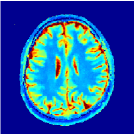

Two sets of experiments were conducted here: first, we used the 2D and 3D acquisition sequences for scanning a healthy volunteer’s brain (real-world acquisitions). Figures 6 and 7 display the parametric maps reconstructed from 2D spiral and radial readouts. We computed the T1, T2 and proton density (PD) maps using baseline reconstruction algorithms ZF, VS, LR, FLOR, AIR-MRF and our proposed LRTV. While baselines use DM either for quantitative inference or also during reconstruction (i.e. AIR-MRF), we further compare the DM-free LRTV’s performance when cascaded to DM, KM and MRFResnet for quantitative inference. For the 3D spiral acquisitions we compared LRTV and its closest competitor VS in Figure 8. Outcomes from other tested algorithm are displayed in the supplementary materials (Figure S5). Since FLOR does not use dimensionality-reduction, our system ran out of memory during 3D reconstruction; hence results are not reported in this case.

VI-E1 Discussion

The LRTV-DM and LRTV-MRFResnet perform on par, and both outperform all tested baselines for reconstructing T1, T2 and PD maps in all acquisition schemes. This can be observed both visually in Figures 6, 7, 8, S2 and S3, and quantitatively in Table IV across all tested metrics. Other baselines were unable to successfully remove the under-sampling artefacts in TSMIs, and these errors propagated to the parameter inference phase and resulted in inaccurate maps. Temporal-only priors incorporated within LR are shown insufficient to regularise the inverse problem and LR sometimes (e.g. 2D spiral acquisitions) can admit solutions with even stronger artefacts than the model-free ZF baseline. This issue was previously studied for other non-Cartesian MRF readouts that similar to our spiral/radial trajectories, miss to sample the corners of the k-space in all timeframes (see section 2.2.2 and figure 2 in [19]). In the absence of reference for the k-space corners information, the LR iterations despite minimising the objective can converge to solutions with high-frequency artefacts, as visible in the computed maps. This highlights the need for adding an appropriate spatial-domain regularisation. FLOR reduces the LR’s artefacts but this improvement is limited because the suggested nuclear norm penalty does not incorporate an explicit spatial regularisation. Further for reducing artefacts, FLOR can introduce an undesirable bias in the computed T1/T2 maps e.g. see error maps in Figures S2 and S3. The non model-based VS baseline incorporates spatial regularisation and results in spatially smoother maps than ZF and LR, but it is unable to output artefact-free images. Further and consistent with our in-vitro experiment, we observe that VS overestimates the T2 values (e.g. in White and Grey matter regions) in tested 2D acquisitions i.e. the spatial regularisation trades off agains the quantification accuracy. The model-based AIR-MRF adds spatial regularisation through 2D/3D low-pass Gaussian filters however this trades off the sharpness of the computed maps and can increase the errors at the tissue boundaries (we searched Gaussian spreads that keep the blurs and high-frequency artefacts minimal). For our acquisition readouts, Gaussian filters performed better than disk filters of [19] for avoiding strong Gibbs artefacts. On the other hand, the spatiotemporally regularised LRTV greatly improves the TSMI reconstructions i.e. 4 dB enhancement compared to the closest competitor baseline (Table IV). This enables computing accurate and aliased-free multi-parametric inference using DM or the DM-free learning-based alternative MRFResnet as visible in Figures 6, 7, 8, S2 and S3. MRResnet and DM score competitive quantitative inference results i.e. T1 and T2 MAPE less than 5% and 9%, respectively (Table IV). KM also outputs comparably accurate T1 maps, however this shallow learning model despite having a model size larger than MRFResnet, is unable to learn accurate T2/PD quantification and it results in poor estimated maps, consistent with our observations in section VI-C.